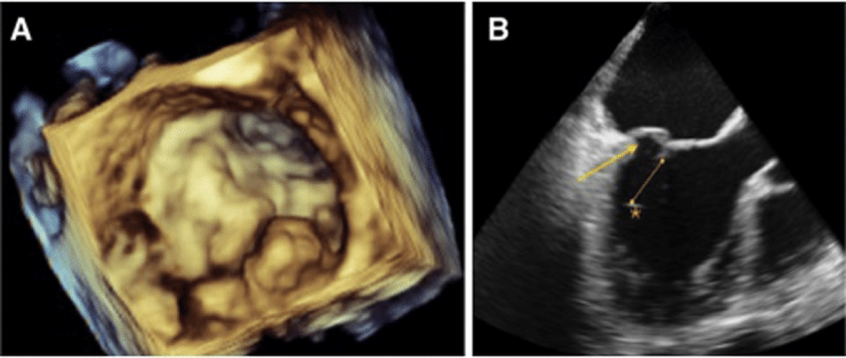

- Transesophageal echocardiogram (TEE): In this type of echocardiogram, the transducer is attached to the end of a flexible tube (probe) that is passed through the esophagus. This allows for more detailed images of the heart since the esophagus is located directly behind the heart.

- We have advanced echo tools such as 3D-Echo imaging and Strain imaging